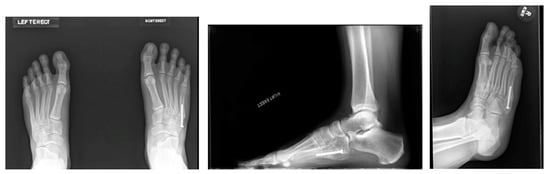

3.2. Diagnosis

3.3. Treatment Considerations